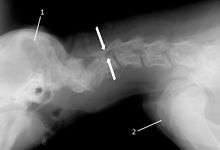

T2 weighted MRI in neutral (A) and linear traction (B) of a seven-year-old Doberman with a two-year history of cervical pain treated with NSAIDs and presented acutely tretraplegic: A C6-C7 and C5-C6 traction responsive myelopathy are evident on MRI. The spinal-cord hyperintensity seen at the C5-C6 is suggestive of chronic lesion and most likely responsible for the chronic history of cervical pain, while the C5-C6 lesion was most likely responsible for the acute tetraplegia.

Same dog (A) treated with double implant (B) three days after surgery: The dog became ambulatory three days after surgery. Four weeks after surgery, it had ataxia without conscious proprioceptive deficits, and three months after surgery, the dog was neurologically normal. The owner reported it had been two years since the dog was able to hold its neck in an elevated position.